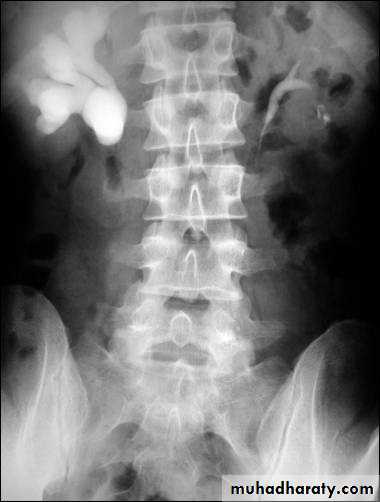

WHAT IS THE MOST APPROPRIATE RADIOLOGICAL MODALITY ?

CT scanWHAT IS THE DIAGNOSIS & THE CAUSATIVE ORGANISM ?

Struvite stone ( MAP stone ).Urea splitting microorganisms.

Urine cultueU / S

KUBURINANALYSIS